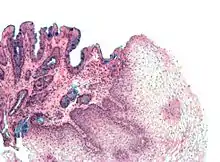

The mucosal layer consists of a epithelial layer, and its underlying supportive tissue, the Lamina Propria. It is separated from the submucosal layer by the Muscularis Mucosa. The epithelial layer varies from section to section of the gut. In the oesophagus it is a non-cornified stratified squamous epithelium; in the stomach it is mainly mucosal cells; the small intestine and large intestine are characterized by absorptive cells, with many mucous producing goblet cells. In the absorptive sections of the intestine, the surface are for absorption is greatly increased by finger-like projections into the lumen called villi, and the absorptive cells themselves also have small projections of microvilli, giving them the appearence of a brush border when viewed with a light microscope.

The surface for absorption is increased in many ways: the mucosa of the small intestine is thrown into folds called rugae; the mucosa itself has numerous finger-like projections called villi, and the epithelial cells are also covered with numerous projections called microvilli. The microvilli give the appearance of a 'brush' on light microscopy; hence the term brush border. The following illustration shows the anatomy of a villi:

Mucous is secreted by numerous goblet cells; other cells are specialized for absorption and are known as absorptive cells. In the base of the crypts are numerous secretory cells which secrete the digestive enzymes of the small intestine. Some of the crypts penetrate into the submucosal layer, forming digestive glands which will communicate with the mucosa via a secretory duct.